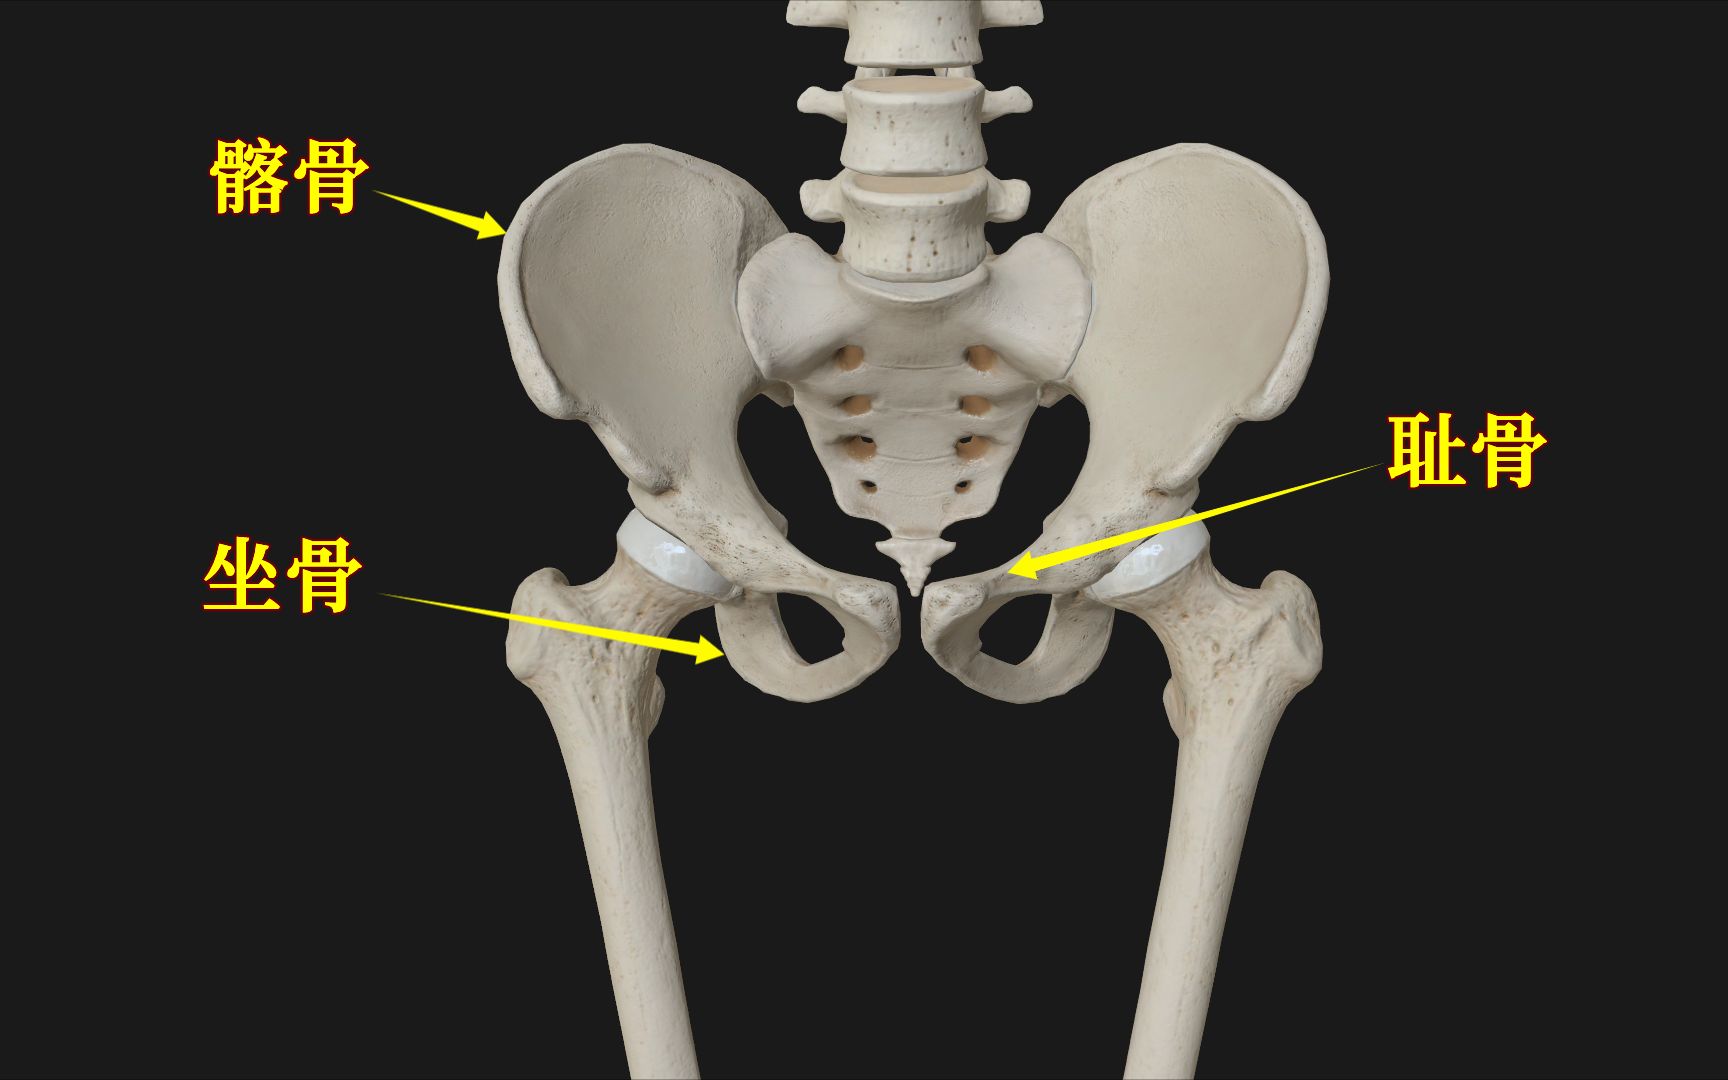

胯骨图片

骨骼日记之髋骨 简介: 髋骨为不规则骨,由髂骨,耻

到青春期结束时,三个区域将融合在一起,到25岁时